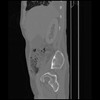

7 CUERPO,CE,Sagittal,3.000,CUERPO,Sagittal,